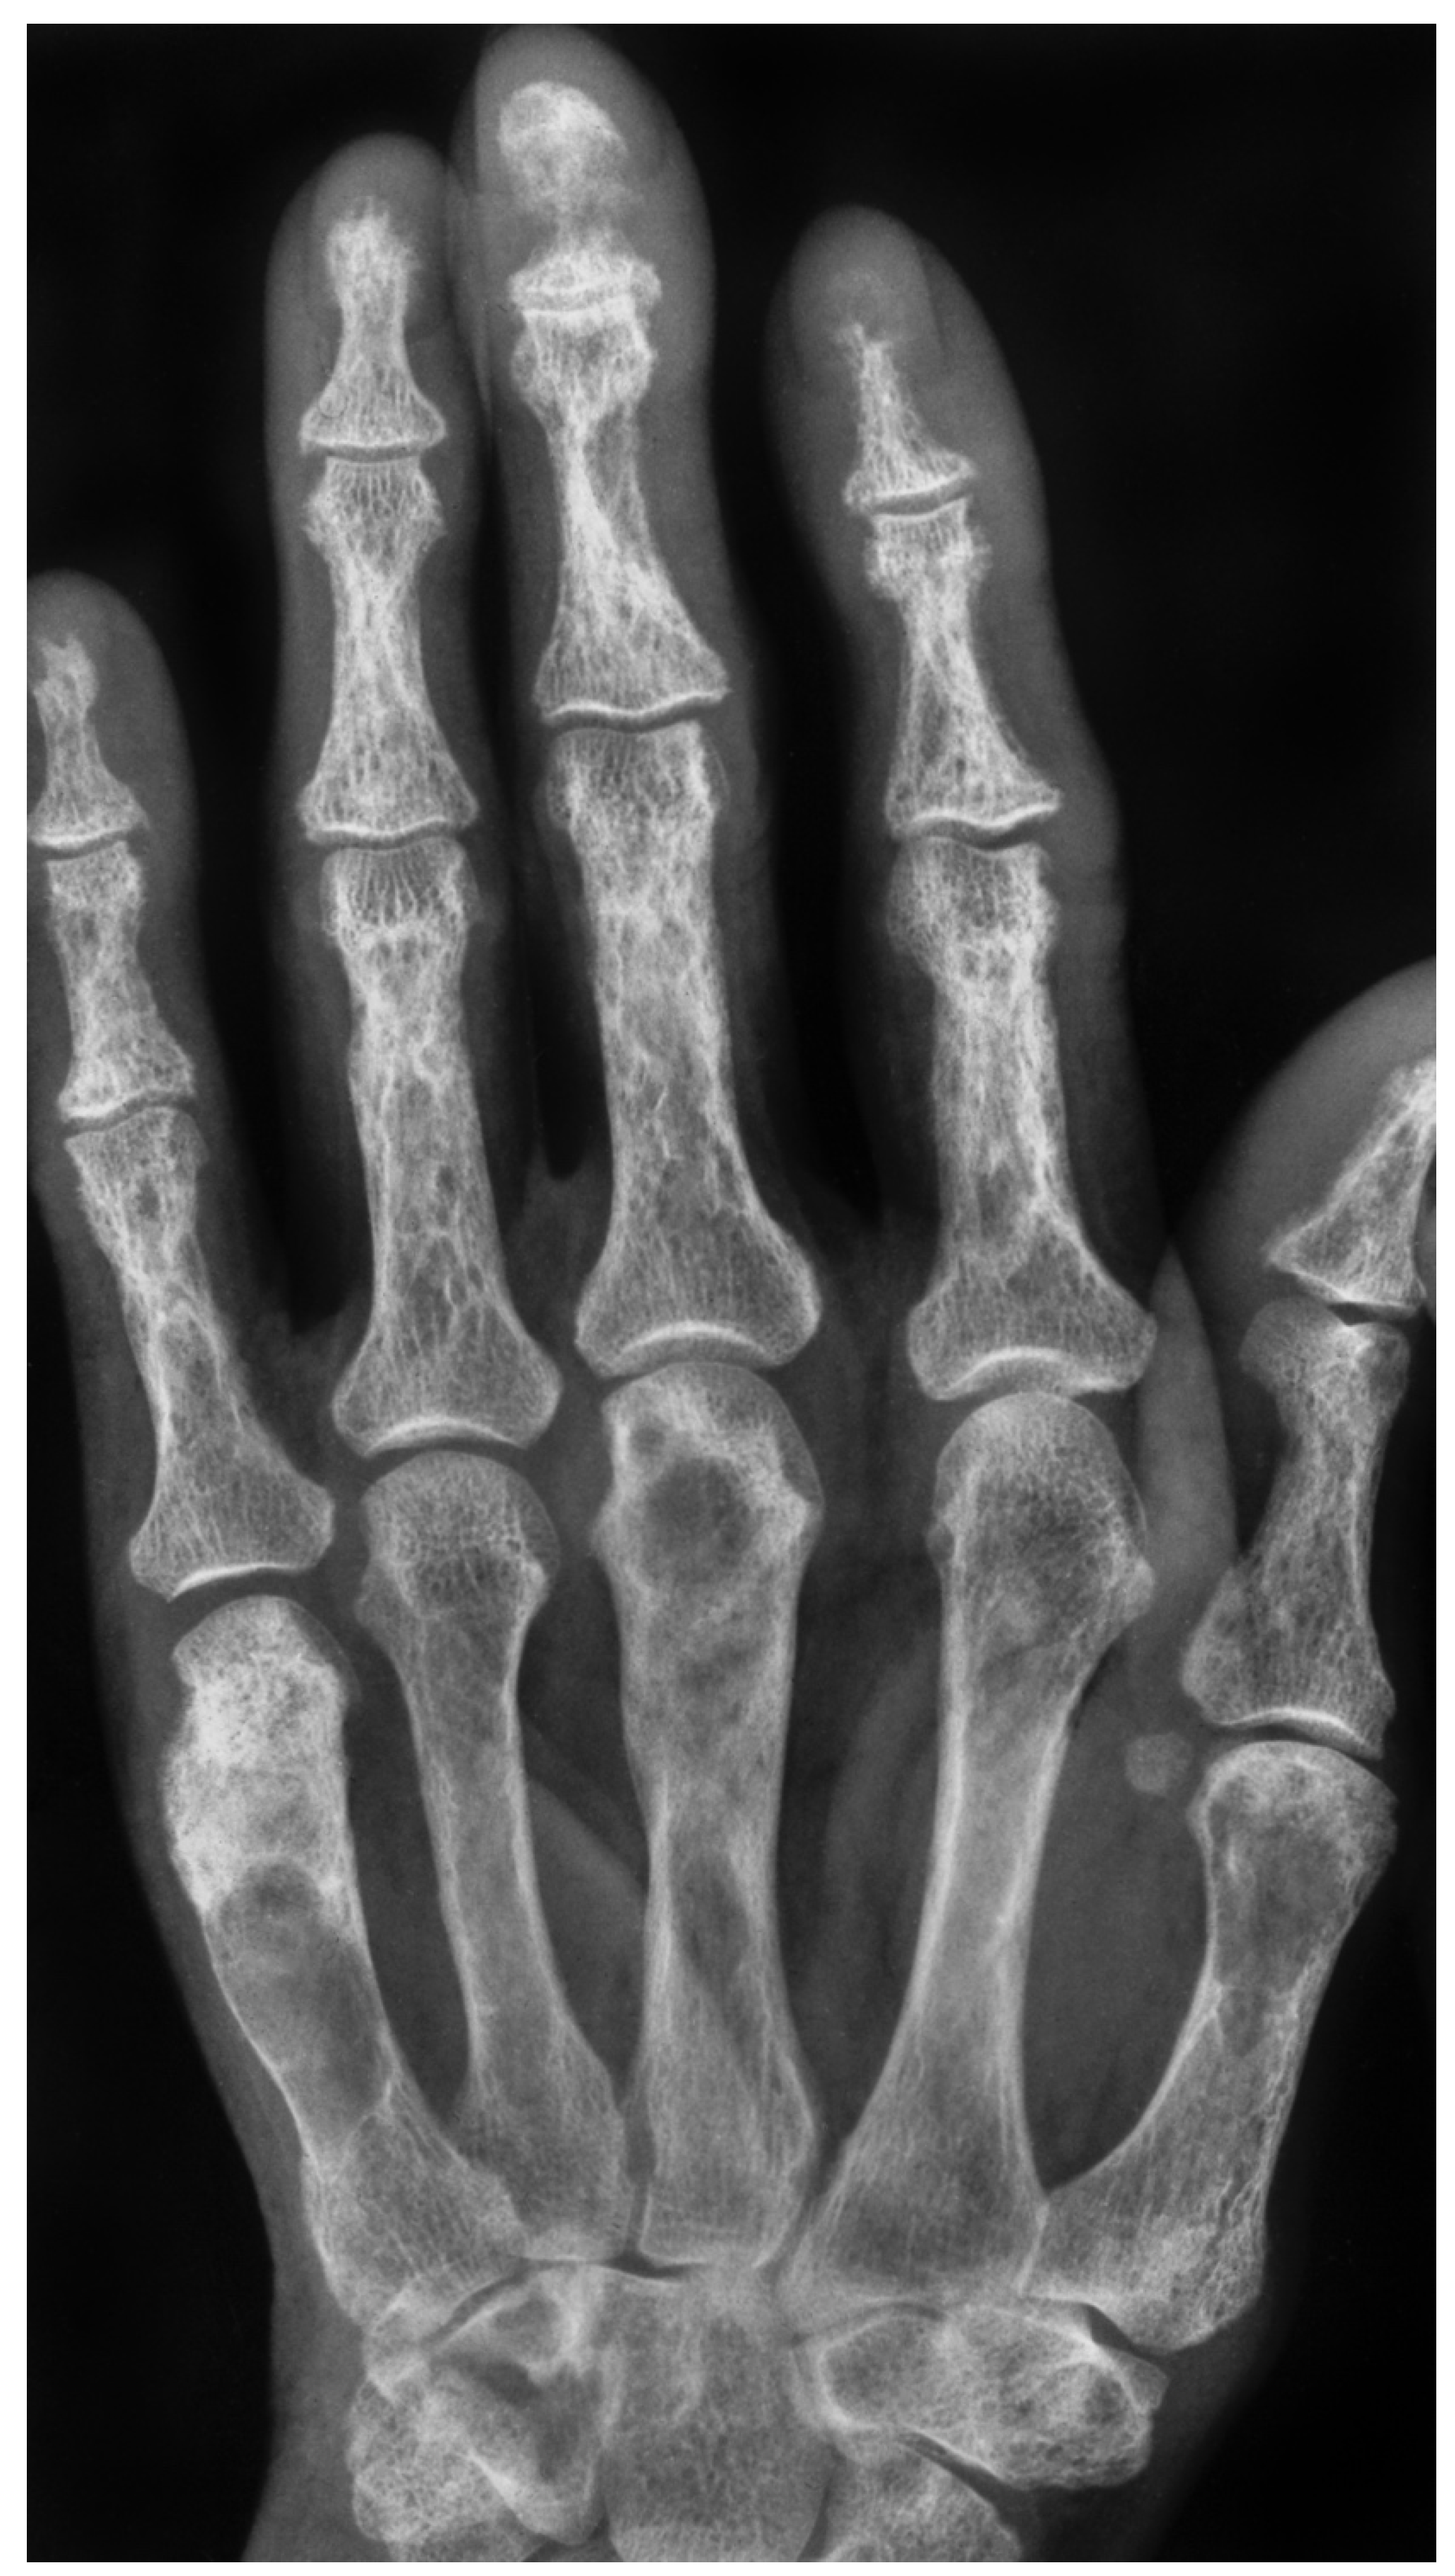

Figure 2. X-ray of a 66-year-old female showing multiple radiolucency’s in the metacarpals and phalanges and subperiosteal erosions quite typical for hyperparathyroidism.